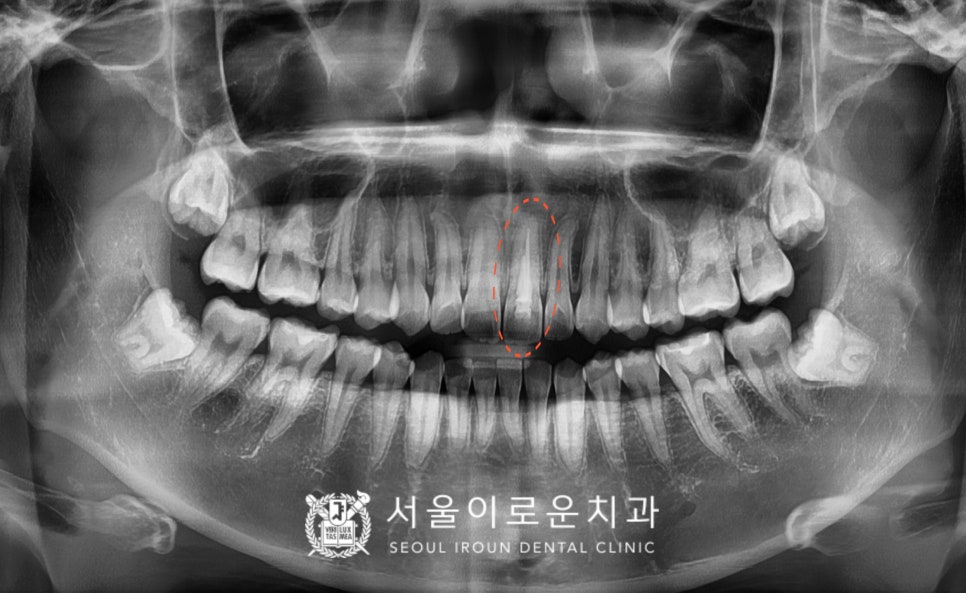

위턱의 왼쪽 위 큰 앞니가(#21)

신경치료되어 있는 상태로

치.아 변색이 관찰되었는데요.

스탠다드 x-ray사진으로 확인한 결과

뿌리 끝까지 충전이 제대로 이루어지지 않아

재신경치료가 필요하였답니다.